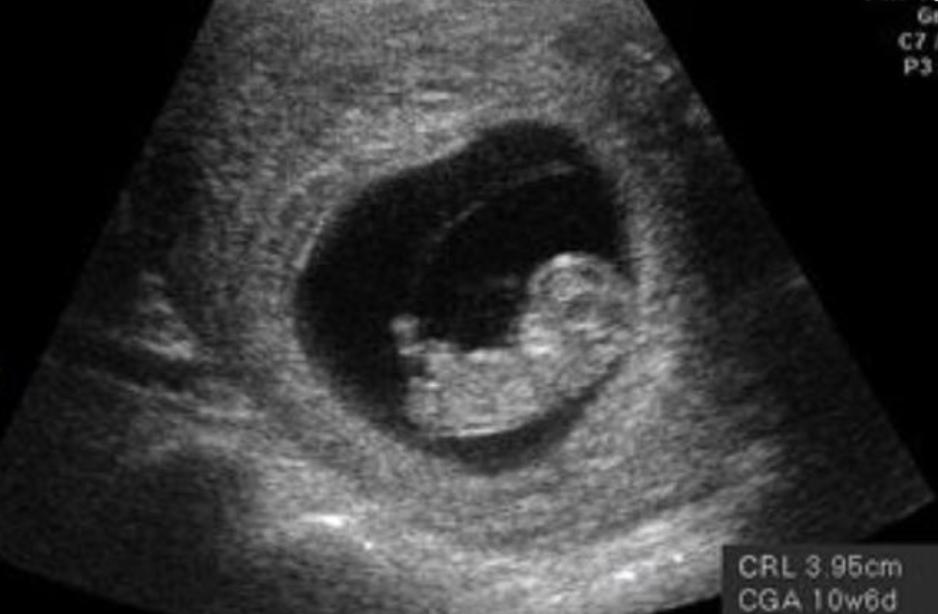

孕10周

在孕10周时,我们的小胎儿已经脱离了不稳定期,开始进入了稳定发育的阶段,这时候的胎儿大约只有梅干那样大小,但是,却已经成为人形,手脚已经可以开始活动,这时候的胎儿各项生命器官已经全部发育形成,可以说是一个袖珍型的小宝宝,这时的他们甚至可以完成吞咽动作。

此时的孕妈咪,几乎感觉不到胎儿的存在,他们就像沉睡中的小宝宝,安静地躺在妈妈的肚子里沉睡。